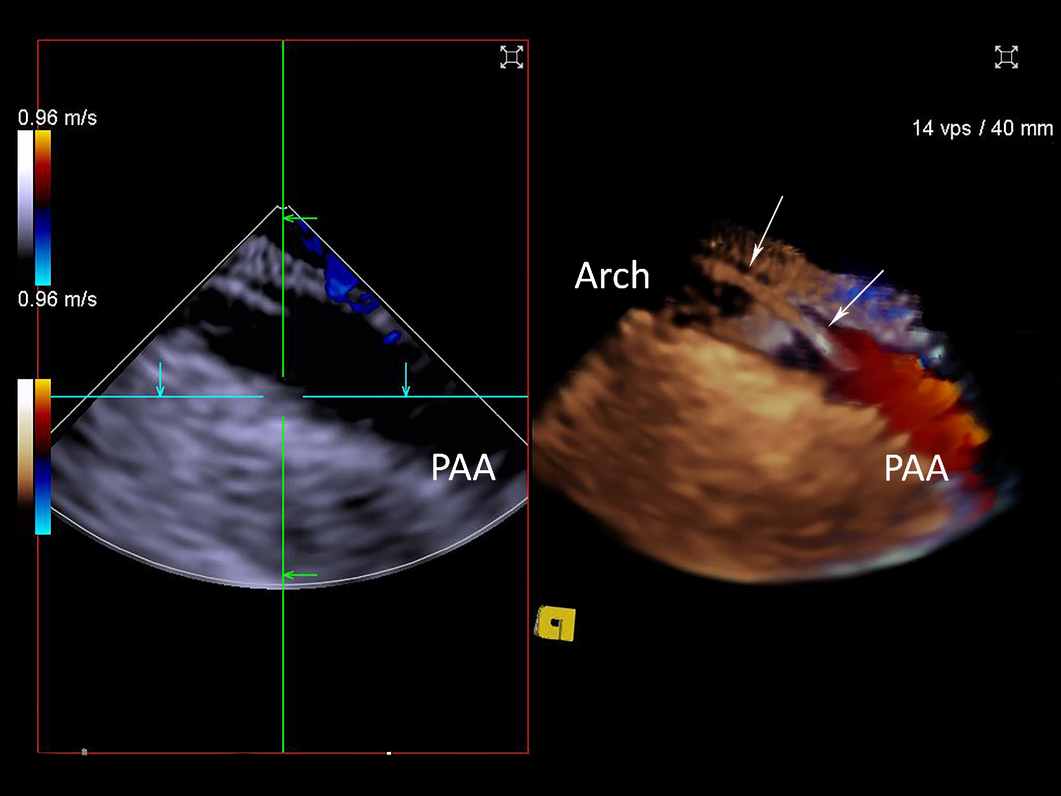

Figure 15

2D ICE (left panel) and 3D ICE Colour Doppler (right panel). Systolic aortic flow is demonstrated in the proximal aortic arch (PAA). The guidewire (white arrows) is clearly visualised within the aortic arch with 3D ICE imaging.